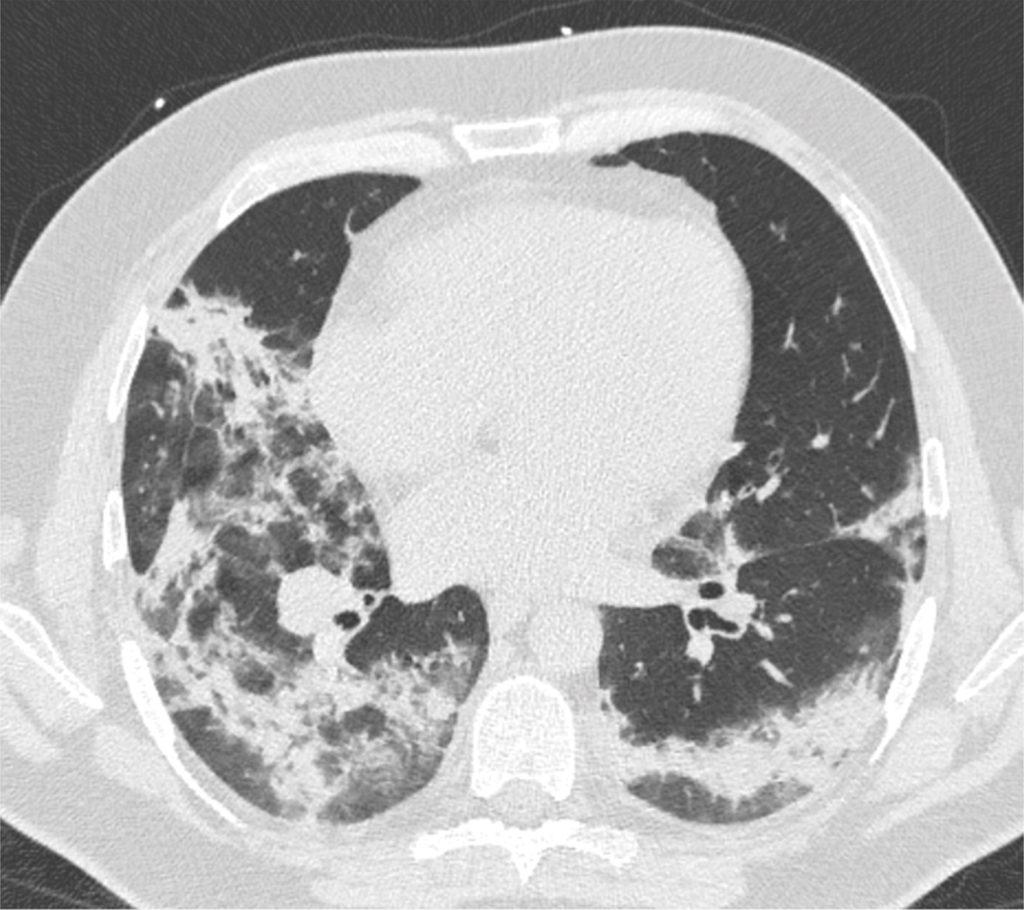

For most of the first year of the pandemic, before any vaccines were available, I saw the effects of the virus on the human body on a daily basis. I’m a diagnostic radiologist, which means I look at CT scans and x-rays. It became clear to me early on that this virus was dangerous. Images like this came across my monitors on a regular basis (source):

One need not be a medical imaging expert to see the impact of the virus on human lung tissue. This is a CT image of the chest. The dark areas are healthy lungs and the patchy white areas are diseased lung tissue caused by viral pneumonia. This is the damage done by the virus in the time it takes the immune system to learn how to detect and destroy it.

Sadly, I still see images like the one above on a regular basis. Each time I do, I lament that the individual is unvaccinated. Many news reports carry a similar message — people who convinced themselves that the virus wouldn’t affect them come to regret the decision to wait. (Here is one such example.)